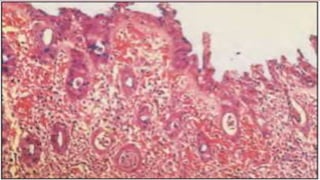

• #11 Campylobacteriosis refers to the disease which Campylobacter species (this includes C. jejuni) cause. onset of disease symptoms usually occurs 2 to 5 days after infection and usually lasts 5 to 7 days, and most of these cases will disappear without treatment. The disease is generally self-limited However, 25% of these patients are likely to have a relapse.  recurrence occurs in children and adults with immunoglobulin deficiencies. Acute C jejuni infection confers short-term immunity. Infection with the organism produces diffuse, bloody, edematous, and exudative enteritis (important virulence factors include: adhesion and invasion of epithelial cells, motility, serum resistance and resistance to bile salts) diarrhea- 10 or more bowel movements per day during the peak of disease, and stools may be bloody on gross examination. severe abdominal pain mimicking acute appendicitis Colitis Bacteremia (rare cases) Crypt abscesses may develop in the epithelial glands, and ulceration of the mucosal epithelium occurs, the inflammatory infiltrate consists of neutrophils, mononuclear cells, and eosinophils. Also on a Physical exam there will be noted weight loss and signs of dehydration